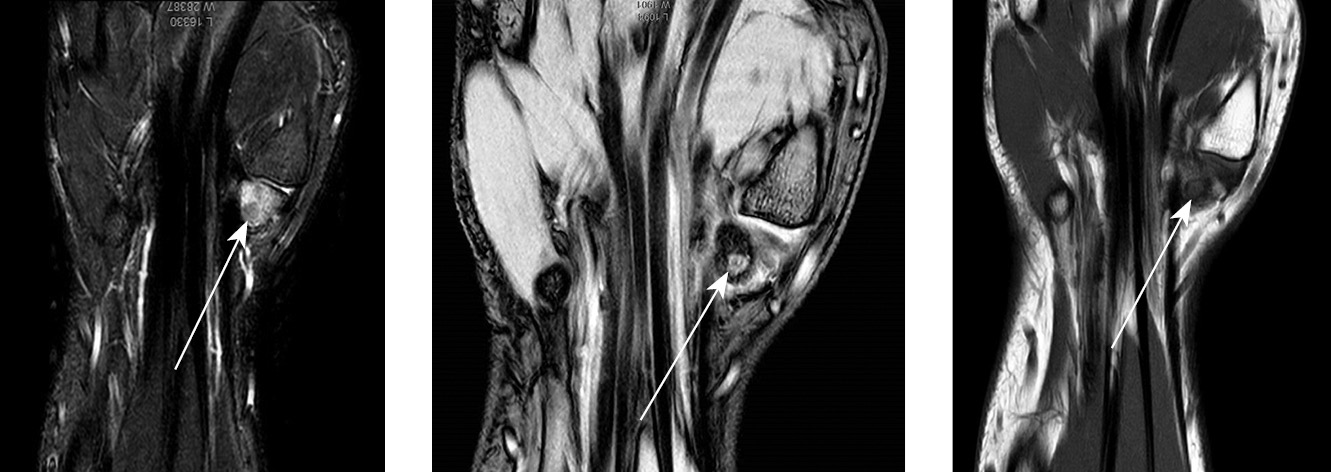

При МРТ определялась зона интенсивного диффузного трабекулярного отека кости-трапеции левой кисти, характеризующаяся гиперинтенсивным МР-сигналом на PD SPAIR и изогипоинтенсивным сигналом на Т1 ВИ. В структуре бугорка кости-трапеции по ладонной поверхности выявлено овоидное образование остеолитического характера диаметром 5 мм, с четкими контурами, окруженное по периферии слабовыраженным ободком остеосклероза. В структуре очага отмечен центральный участок остеосклероза низкоинтенсивного сигнала. Данное патологическое образование характеризовалось преимущественно изогипоинтенсивным сигналом на Т1 ВИ и PD SPAIR. Наблюдали умеренно выраженный отек параоссальных мягких тканей левой кисти соответствующей локализации (рис. 3).

Рис. 3. Пациент П., 17 лет. Магнитно-резонансные томограммы левой кисти, демонстрирующие локализацию «гнезда» опухоли (указана стрелкой)